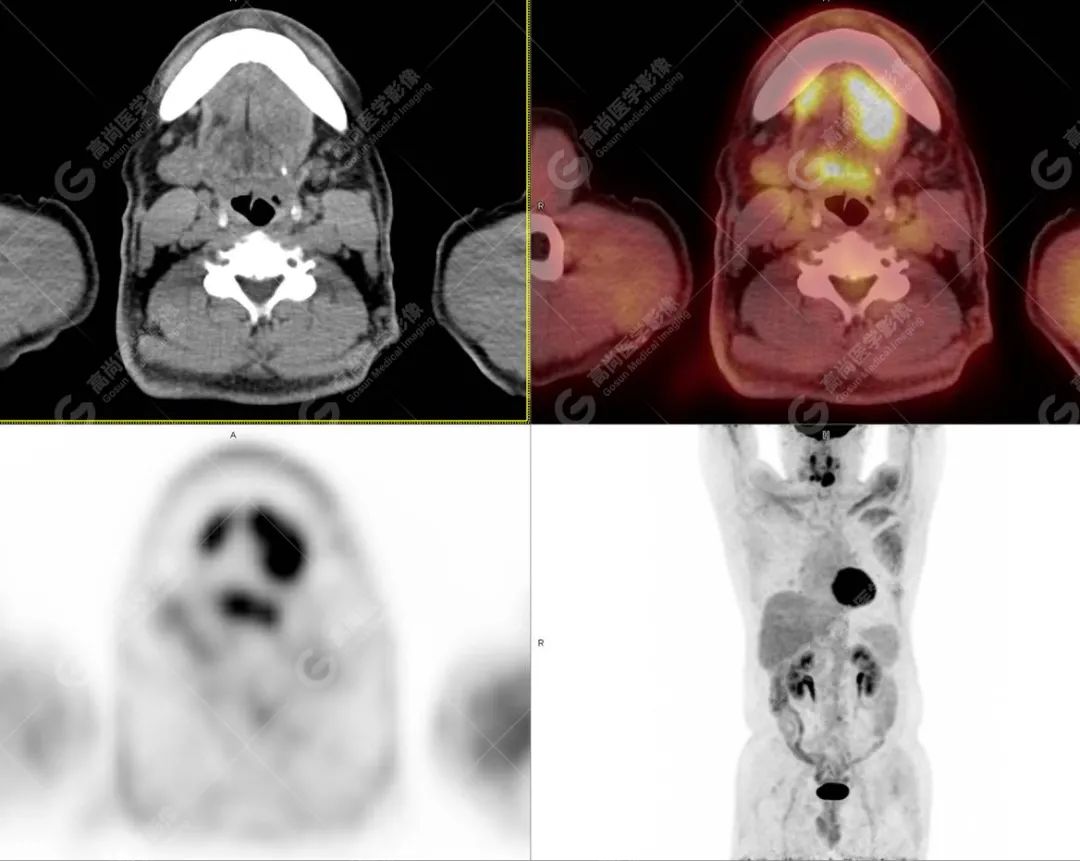

PET/CT影像图

图2

影像诊断: 1.舌体部左右侧软组织明显增厚,密度稍低,左侧为著,代谢异常增高, 考虑为舌癌,并口底受侵, 建议穿刺病理学检查明确。

2.双肺多发大小不等实性结节,部分代谢轻度增高, 考虑为转移瘤。